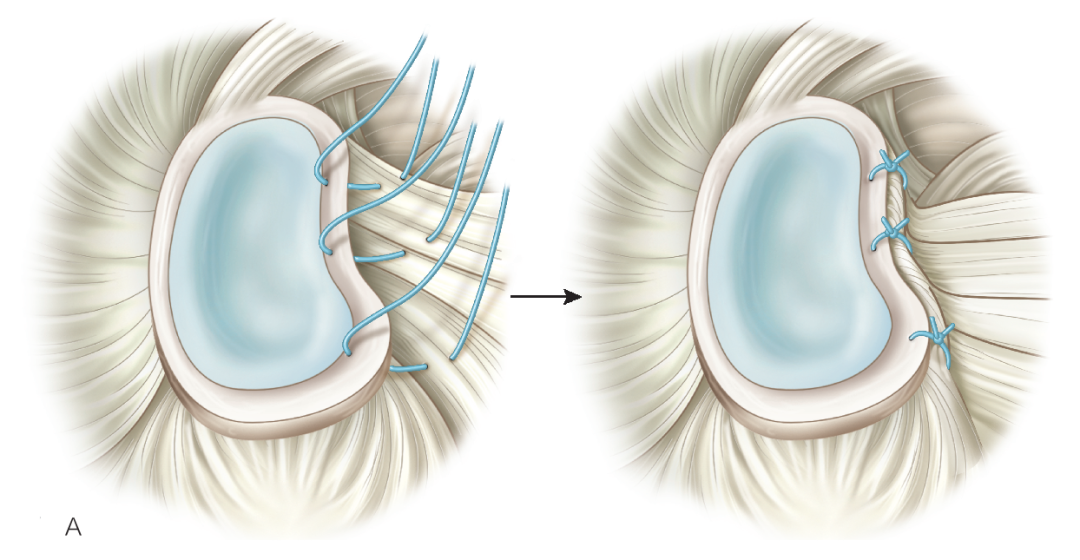

上盂唇修复

创建前方和后方入路时,与关节盂面成恰当角度,以便锚钉的置入。 高位和外侧放置前方入路可以有效地进行单纯上盂唇的修复。该入路位于肩袖间隙的高位和外侧,用腰椎穿刺针进行定位。非刚性套管有助于在肱二头肌腱附着部后方置入锚钉。 可用于 SLAP 修复的辅助入路包括 Wilmington 入路(肩峰后外侧角前方、外侧各 1 cm 处)或 Neviaser 入路(锁骨、肩峰、肩胛冈组成的三角形内,肩峰内侧 1 cm 处)。

B. 应首先用腰椎穿刺针确定辅助入路的恰当位置和方向。然后在皮肤上做一个小切 A B 口,钻头导向器置入关节。